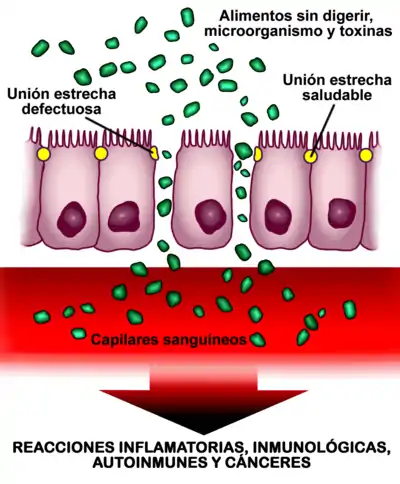

Aumento de la permeabilidad intestinal

Además de por inhalación, el asma puede ser causada por reacciones a alimentos o sustancias que penetran a través del intestino. Por esta razón, el aumento de la permeabilidad intestinal parece desempeñar un papel clave. Se ha demostrado que aproximadamente el 40 % de las personas asmáticas tienen una mayor permeabilidad intestinal.[8]

El intestino posee en su interior una capa de células que forman una barrera. Su misión es, además de digerir nutrientes, actuar defendiendo al organismo del enemigo exterior del ambiente (sustancias que ingerimos y microorganismos presentes en el intestino). Esto lo logra manteniendo cerradas las uniones estrechas intercelulares (los "poros" del intestino), para impedir el acceso descontrolado de sustancias, toxinas, químicos, microorganismos y macromoléculas, que de lo contrario podrían pasar al torrente sanguíneo. Cuando dichas uniones estrechas intercelulares no funcionan bien y en lugar de estar cerradas o prácticamente cerradas, como deberían estar, están abiertas sin control, se produce un aumento de la permeabilidad intestinal ("poros" demasiado abiertos). Esta apertura provoca que entren sustancias en el cuerpo y que, dependiendo de la predisposición genética de la persona, puedan desarrollarse enfermedades autoinmunes, inflamatorias, infecciones, alergias, asma o cánceres, tanto intestinales como en otros órganos.[8]

Los dos factores más potentes que provocan aumento de la permeabilidad intestinal son ciertas bacterias intestinales y la gliadina[8] (principal fracción tóxica del gluten), independientemente de la predisposición genética, es decir, tanto en celíacos como en no celíacos.[28][29] Otras posibles causas son la prematuridad y la exposición a radiación, quimioterapia o ciertas toxinas.[8]